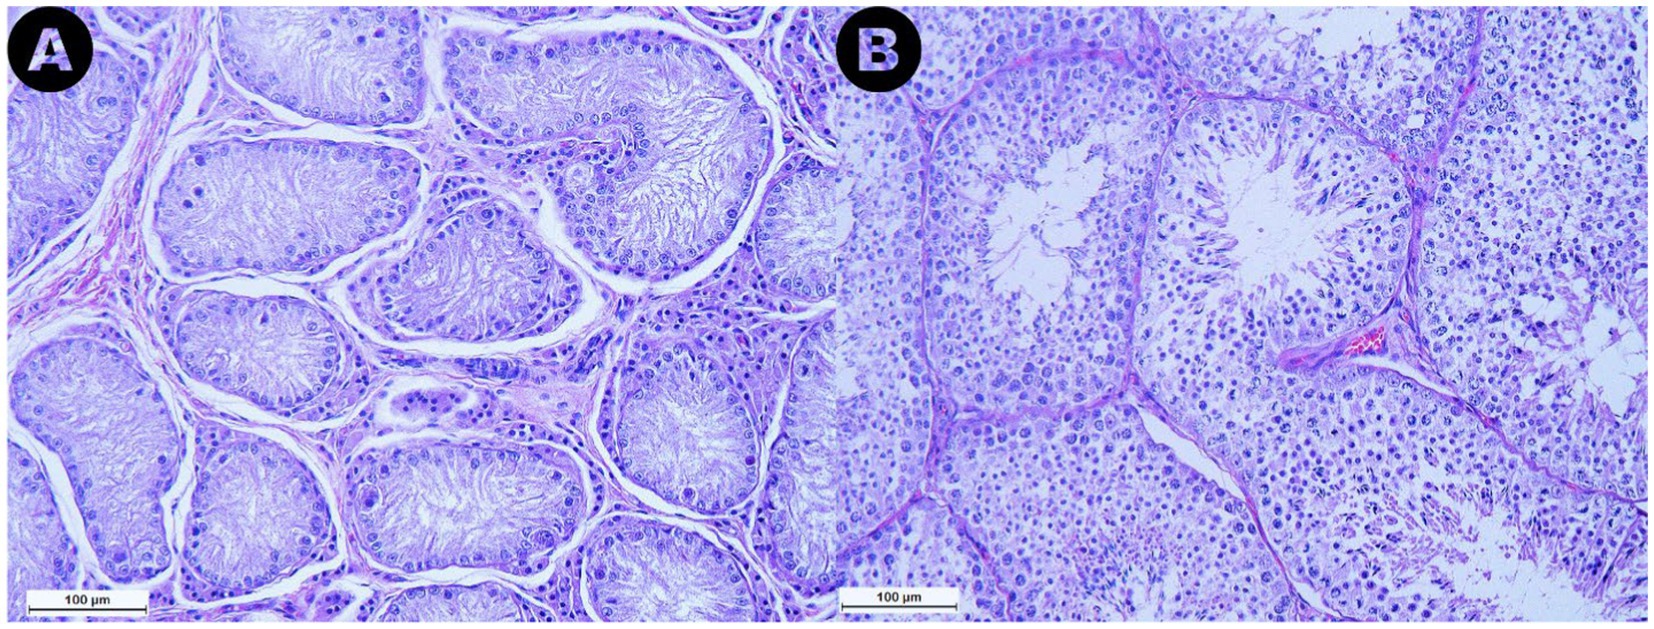

Las muestras analizadas de la categoría RET exhibieron túbulos seminíferos con pocas células germinales, con el 76,7% de las secciones de túbulos evaluadas clasificadas como túbulos solo de células de Sertoli. Además, se observó una marcada reducción o ausencia de la luz (Figura 4A). Además, se evidenció la degeneración seminífero de los túbulos, caracterizada por una pérdida general de los detalles celulares. La membrana basal que rodea los túbulos parecía engrosada en comparación con las muestras de los grupos CONTRA y DES. Además, en el espacio intersticial de los testículos RET, se observó subjetivamente un aumento en el número de células de Leydig, acompañado de una mayor cantidad de tejido conectivo (Figura 4A), en comparación con las muestras de DES (Figura 4B).